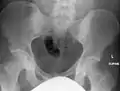

تبكل عظام الورك بالأشعة المقطعية.